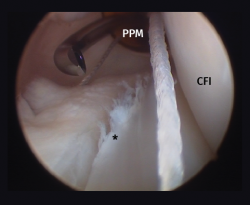

Other tests that contribute to the diagnosis are stress valgus radiographs (local anesthesia infiltration is advised in order not to underestimate the test), magnetic resonance imaging (MRI) and arthroscopic exploration (Figure 1).

[[{"fid":"4710","view_mode":"default","fields":{"format":"default","alignment":""},"type":"media","field_deltas":{"1":{"format":"default","alignment":""}},"link_text":null,"attributes":{"class":"media-element file-default","data-delta":"1"}}]]

Other diagnostic tests are radiographs under stress varus conditions. We can find indirect radiological signs such as Segond fracture and the arcuate sign. MRI is of great help. Gelber et al. recently reported that over 80% of a group of world experts in the treatment of posterolateral angle injuries agree on the usefulness of MRI in the diagnosis of these lesions(17). Lastly, arthroscopy can offer additional information in the surgical cases (Figure 2).

[[{"fid":"4711","view_mode":"default","fields":{"format":"default","alignment":""},"type":"media","field_deltas":{"2":{"format":"default","alignment":""}},"link_text":null,"attributes":{"class":"media-element file-default","data-delta":"2"}}]]